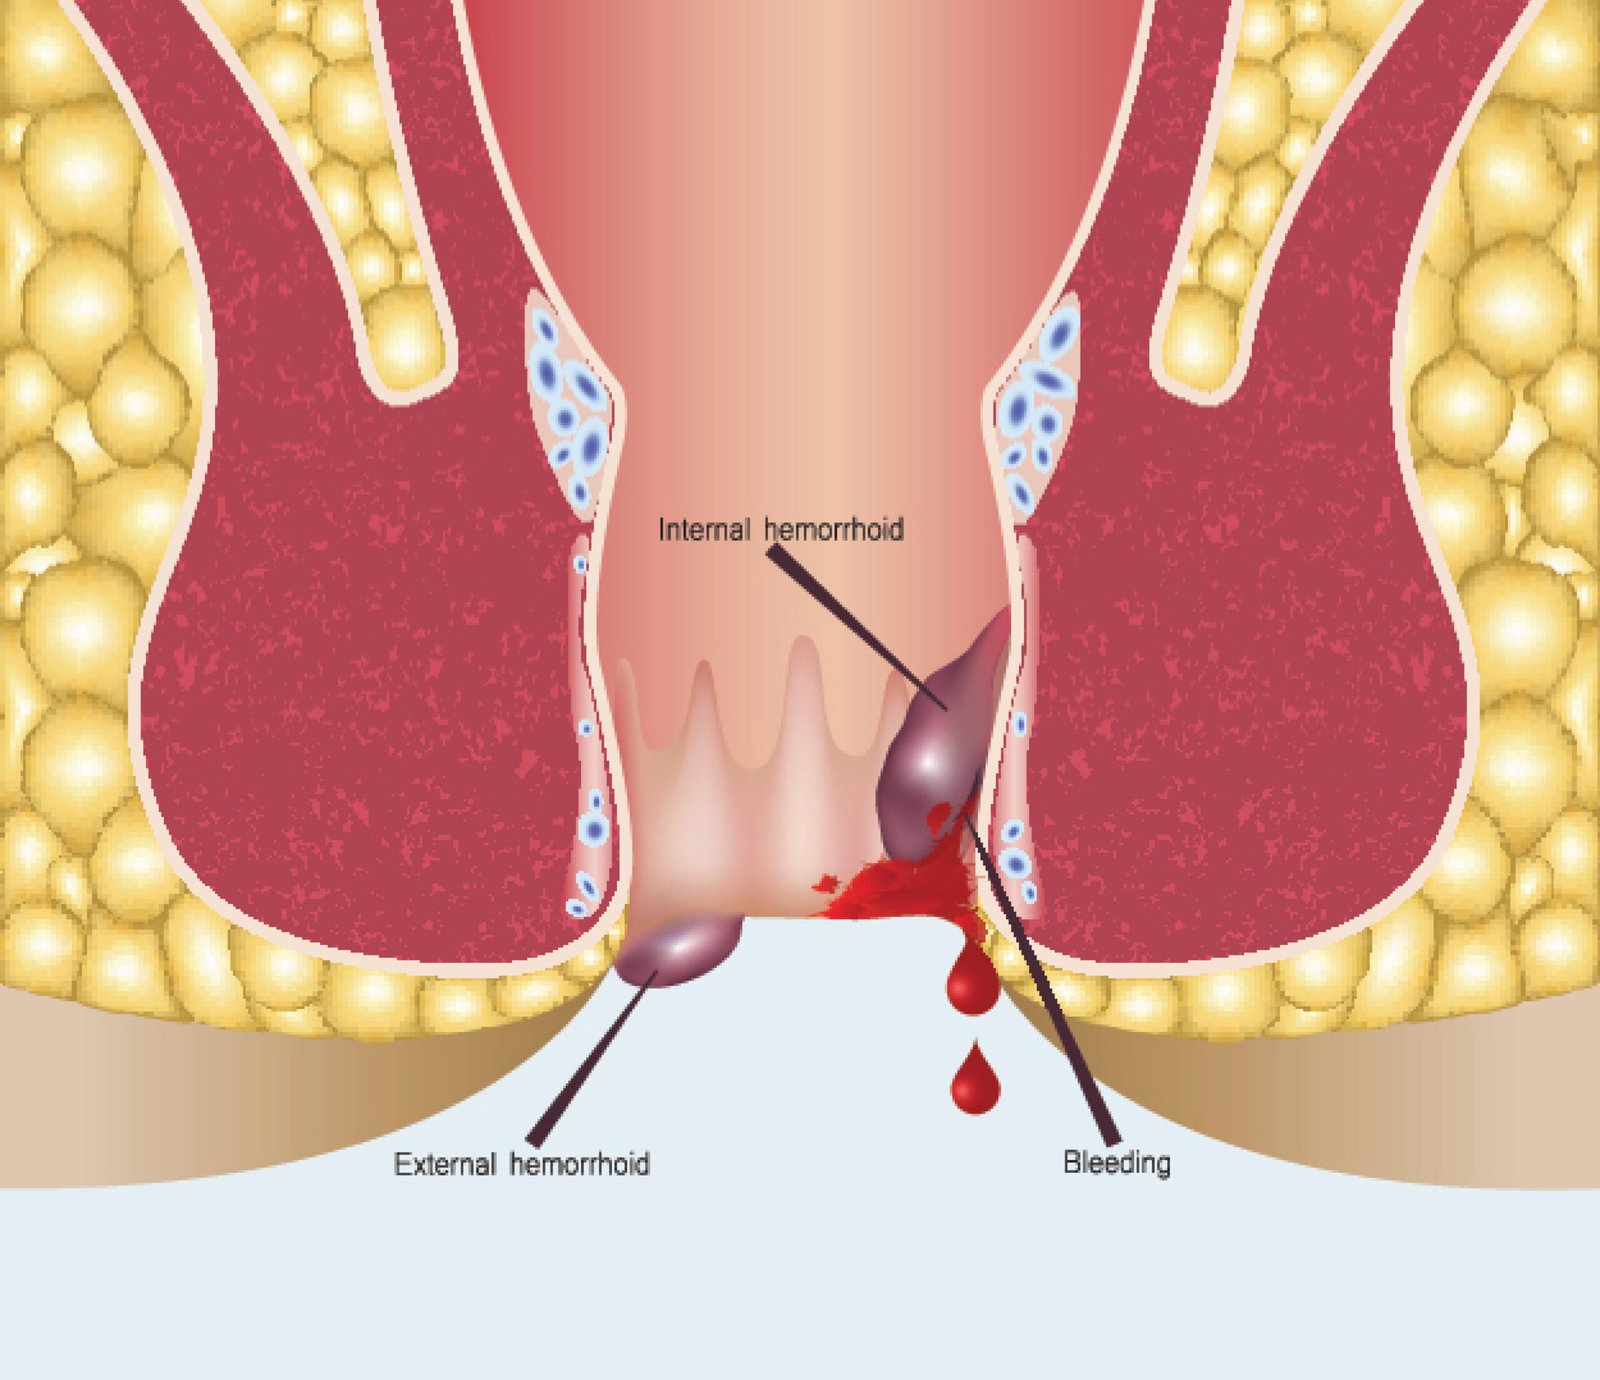

We provide laser and conventional surgical treatments for haemorrhoids, fissures, and fistulas. Our procedures are designed to reduce pain, bleeding, and recovery time. Consultations ensure the best treatment approach for every patient. Quick relief with long-lasting results.